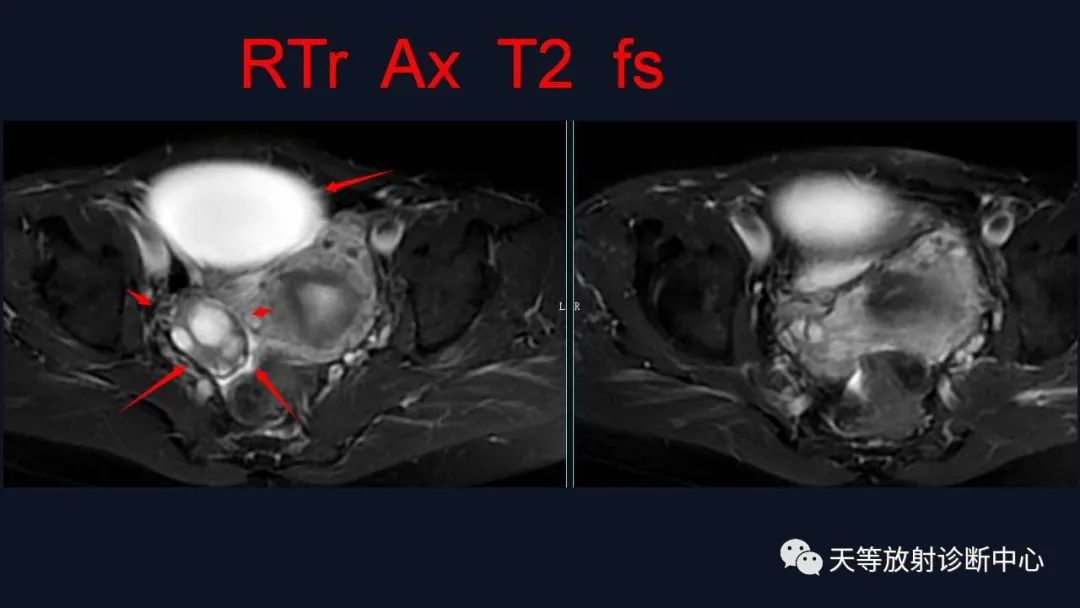

1、浆液性囊腺瘤 :浆液性囊性肿瘤较常见,浆液性肿瘤好发的平均年龄为40岁以上,表现为纯囊性,可呈多囊改变,T1WI呈低信号、T2WI呈高信号、DWI呈低信号,增强后无实性成分强化。

交界性肿块呈囊实性、多房改变, T1WI呈高信号、T2WI呈高信号、病灶实性部分DWI以较高信号为主,增强后实性成分均呈结节状强化。